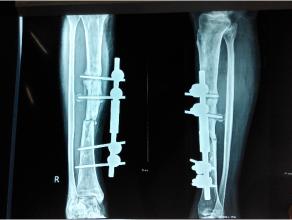

骨科常見(jiàn)疾病——骨不連

骨不連:

骨折不愈合稱之為骨不連。骨組織具有自身修復(fù)的強(qiáng)大能力,當(dāng)骨折給予適當(dāng)?shù)闹委?,大多?shù)骨折都會(huì)很好愈合。然而,一部分骨折卻難以愈合。當(dāng)骨折愈合比較緩慢,稱為延遲愈合。當(dāng)骨折不能愈合,則稱為骨不連。在所有骨折病人中,大約5%的患者愈合困難。由于骨折部位的持續(xù)活動(dòng),骨不連通常伴有疼痛,大大降低了患者的生活質(zhì)量。

易發(fā)生骨不連的部位:

任何一處骨都可以發(fā)生骨不連,但有幾處骨骼血液供應(yīng)差,特別容易發(fā)生骨不連,包括:舟骨;距骨;股骨頸;第五跖骨;脛骨中下段等。

治療方法:

在確定骨不連的治療時(shí),必須考慮以下因素:明確原因,骨不連的部位(具體的骨及骨內(nèi)的位置),骨不連的類型,之前的治療,X線表現(xiàn),以及一系列其他病人的具體特點(diǎn)。

在廣義上,治療計(jì)劃應(yīng)包括改善局部生物學(xué)行為或/和加強(qiáng)其機(jī)械穩(wěn)定性。常用的改善局部生物性狀的治療方法包括:去除感染灶,骨移植,骨髓移植和應(yīng)用Ilizarov方法。提高機(jī)械穩(wěn)定性的方法包括:鋼板螺釘內(nèi)固定術(shù),髓內(nèi)釘內(nèi)固定和外固定架。